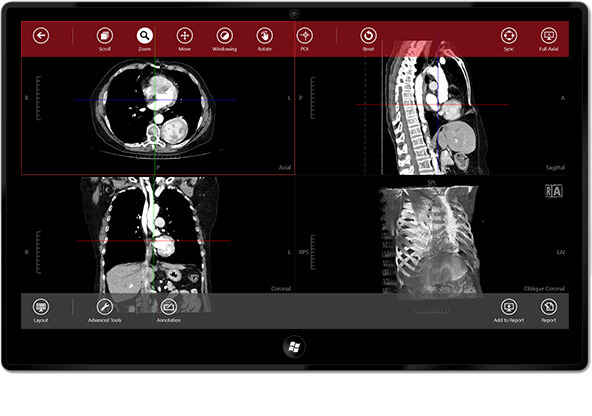

The Navegatium DICOM viewer has been designed especially for touchscreen computers and tablets, and when used on these devices can be very fast and simple to use. It offers MPR, MIP, and simulated reconstructions. The layout and views can be customized as per user preferences. It can be directly integrated with PACS, but does not offer storage, importing and sharing.

It may be slightly awkward to use without a touchscreen. This application only runs on higher versions of Windows. It lacks advanced features, but is useful for basic use.

| 4. | Navegatium | Windows 8.1 or higher | Can integrate to PACS, no cloud storage | Y | Y | N | N.A. | 60 MB | i3 processor/ 4 GB RAM; Directx10 or higher graphics chipset | Freeware ; not FDA approved |